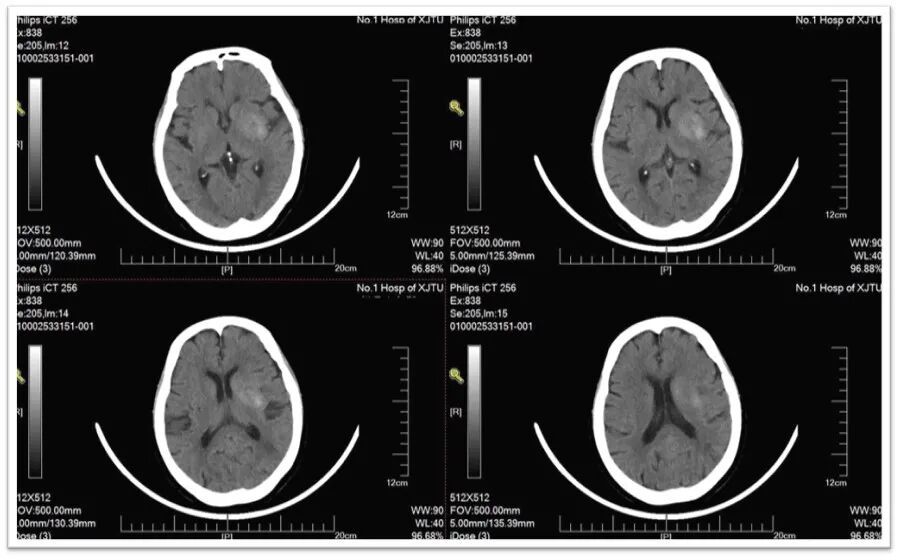

术后即刻NCCT:左侧侧脑室旁基底节区造影剂外渗;

术后6小时NCCT

术后24小时NCCT

术后3天DWI:左侧大脑半球额颞顶叶多发散在新鲜梗死灶。

术后3T天ADC:

术后3天MRA:

术后24小时NIHSS:6分,出院时NIHSS:4分,出院时mRS:1

一月后mRS:1。